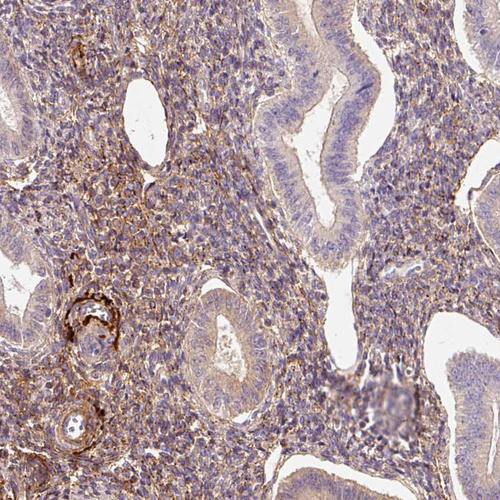

Immunohistochemical staining of human lung shows moderate extracellular space positivity in pneumocytes and macrophages.